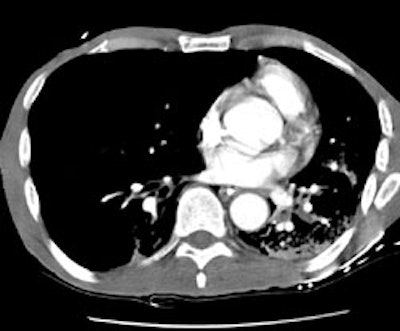

CT PE exam: Alternative diagnosis

The CT PE exam shown below demonstrates bilateral air space disease and a right pneumothorax that was not evident on the patients CXR (Click CXR to enlarge). The CT-PE exam can suggest an alternative diagnosis to explain the patients symptoms in 10-50% of cases.